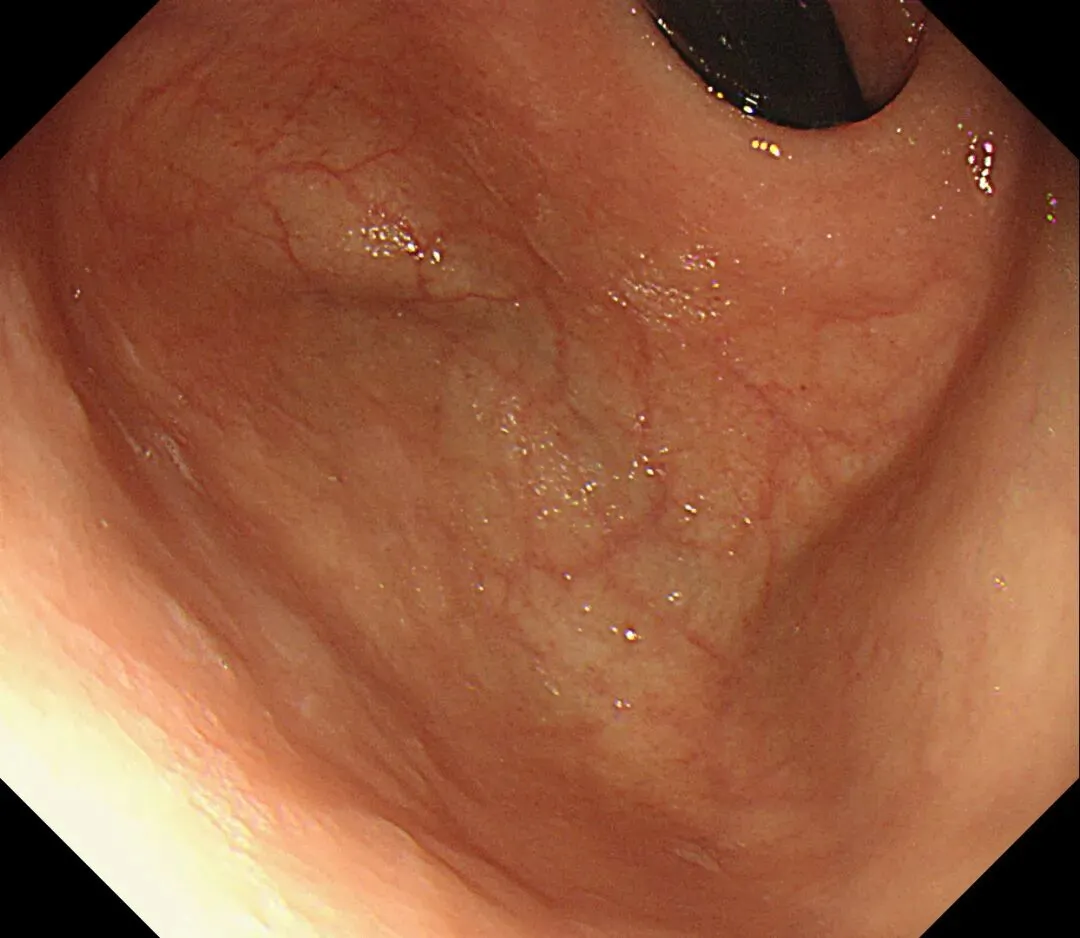

这一期不用码字,挺好的,很可惜一直没机会听过胡导讲的关于这个“花环征”的大课,学习内容来源于雨夜大师的号花环征:AIG背景的胃食管结合部的黄色颗粒状隆起及半透明“泡状”改变

补充自己在两例A型胃炎/AIG 观察到的“花环征”,巩固下学习效果。。。

case1:

1.白光表现为胃食管交界处黄色颗粒状隆起及半透明“泡状”改变

2.窄带光下可见颗粒状隆起呈褐色改变,放大可见细微网状血管结构及半透明“泡状”改变

3.典型病理是鳞状上皮局灶性变薄及黏膜固有层显著增生、扩张的贲门腺。